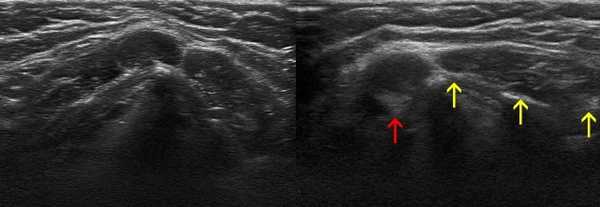

Аденопатия инфекционного генеза на сонограммах характеризуется следующими изменениями в строении ЛУ:

- нечеткостью границ;

- увеличением в диаметре - в среднем до 2-4 см;

- неоднородностью структуры;

- нарушением целостности капсулы - показатель прорыва воспалительной жидкости в соседние ткани.

Осложнения при заболеваниях ЛОР-органов влияют на особенности УЗ-визуализации лимфоузлов шеи - последние на экране ультразвукового сканера могут выглядеть как анэхогенные жидкостные образования либо как участки низкой и высокой эхогенности, чередующиеся друг с другом. Указанные изменения на снимках характерны для гнойного расплавления и формирования аденофлегмоны.

- в ответ на воспалительные (микробной или вирусной этиологии) процессы лимфатические узлы отвечают изменением эхоструктуры в виде улучшения четкости дифференциации лимфатических узлов на фоне окружающих тканей. При этом отмечается увеличение толщины гипоэхогенного изображения коры лимфатического узла. Гиперэхогенное изображение области ворот сужено. Процесс выздоровления (возвращение лимфатического узла в состояние покоя на фоне медикаментозной терапии или за счет собственных защитных сил) характеризуется сначала уменьшением толщины корковой части и общих размеров лимфатического узла, а затем практически полным отсутствием его дифференциации с окружающими тканями;

- у больных с воспалительными процессами на фоне синдрома иммунодефицита не было отмечено УЗ признаков активизации коры, что в контрольной группе проявлялось увеличением толщины области ворот и тенденцией к округлой конфигурации. При динамическом наблюдении УЗ-картина свидетельствовала о вовлечении в процесс все новых лимфатических узлов. "Старые" же лимфатические узлы на фоне проводимой терапии не имели УЗ признаков положительной динамики.